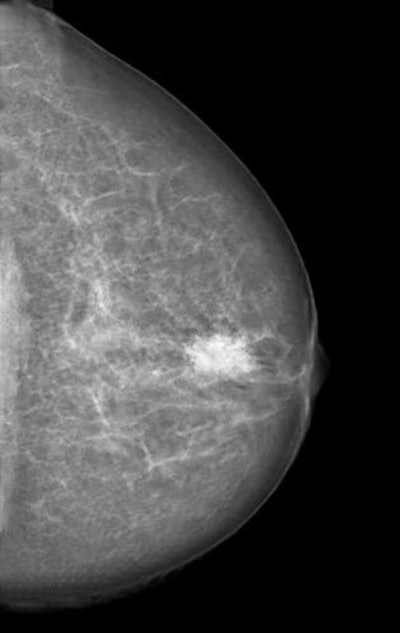

Mammogram manipulated with a neural network-generated mass. Image courtesy of RSNA and Dr. Anton Becker.The model then learned how to recognize normal commands and to predict if new commands are legitimate or not, according to the researchers. After the system detects a malicious command sent to the device by an attacker, it alerts the operator before the command is executed.

Meanwhile, researchers from University Hospital Zurich and ETH Zurich in Switzerland described how they trained a cycle-consistent generative adversarial network (CycleGAN) to convert mammography images showing cancer into normal studies, as well as to convert normal control images into studies that show cancer. After three radiologists reviewed all of the images, none could reliably distinguish between the genuine and the modified cases.